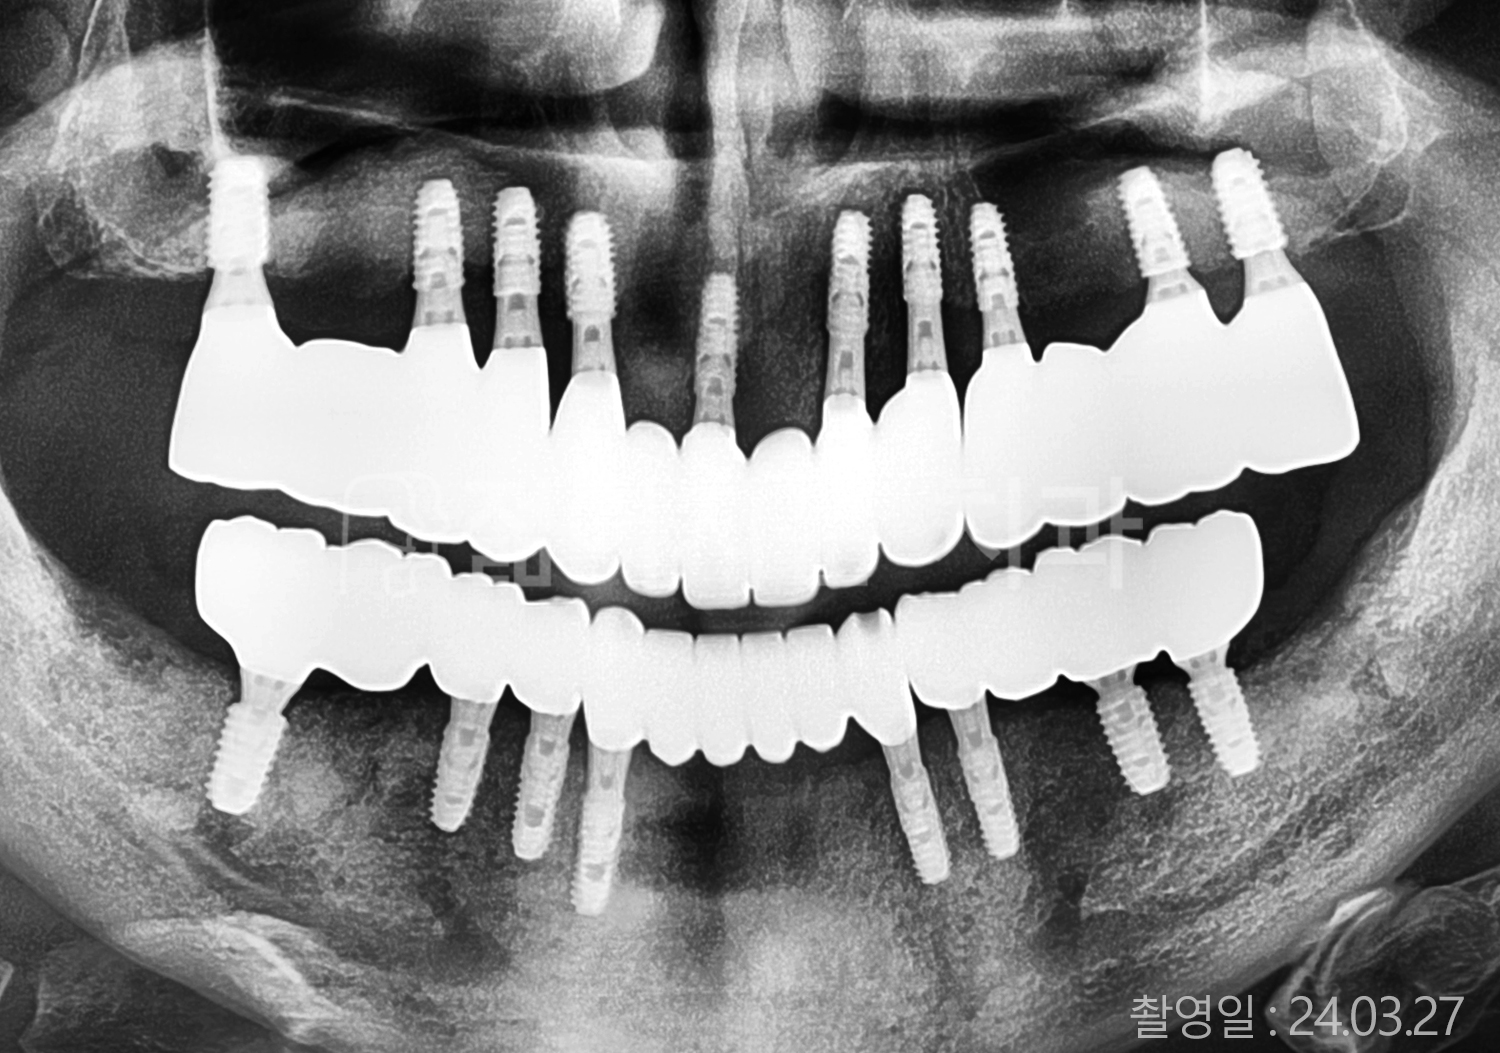

• 50대 고혈압, 당뇨, 고지혈증 전체치아 10개 이상 임플란트

• 60대 골다골증, 간경화 전체치아 10개 이상 임플란트

• 60대 고혈압, 고지혈증 전체치아 10개 이상 임플란트

• 50대 고혈압, 당뇨 전체치아 10개 이상 임플란트

• 60대 고혈압 전체치아 10개 이상 임플란트

• 60대 전체치아 10개 이상 임플란트

• 60대 고지혈증 전체치아 10개 이상 임플란트

• 40대 전체치아 10개 이상 임플란트

• 70대 전체치아 10개 이상 임플란트